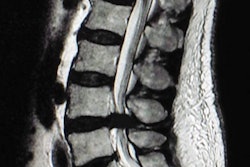

Injuries to the wrist are difficult to assess noninvasively, due to the wrist's small size and tricky anatomical structures such as intercarpal ligaments, the triangular fibrocartilage complex, and articular cartilage. However, a group from Lund University Hospital in Sweden found that 7-tesla MRI improves anatomical visualization and image quality over 3-tesla imaging, and this could lead to better detection and management of pathologies.